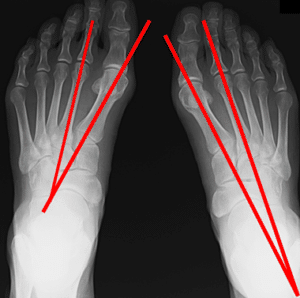

ひざ 【葛飾区金町のやぎはし整体院】ひざの整体 母趾を整える 外反母趾がひざの痛みの原因になる《金町のやぎはし整体院が解説》 外反母趾の病因 様々な形状や性質、種類の靴が作られ、それを履くことや最近の生活様式によって、急速に増加してきています。 その要因として、以下などが密接に関わりあって発生します。 外反母趾になる要因 土踏まず(内側縦アーチ)の低下=扁平足 横アーチの低下 中...